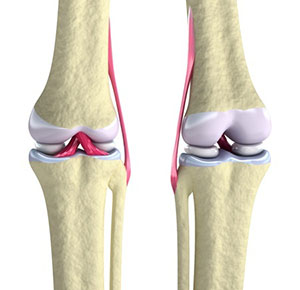

The pink portions are ligaments that hold bones together. |

What do ligaments do? Ligaments allow bones to move around a joint by adding stability. For example, your knee is made mostly of a hinge joint that allows the femur and tibia to move back and forth. The ligaments around this joint prevent the bones from moving side to side. Ligaments also help to prevent joints from going in the wrong direction.

What do ligaments do? Ligaments allow bones to move around a joint by adding stability. For example, your knee is made mostly of a hinge joint that allows the femur and tibia to move back and forth. The ligaments around this joint prevent the bones from moving side to side. Ligaments also help to prevent joints from going in the wrong direction.